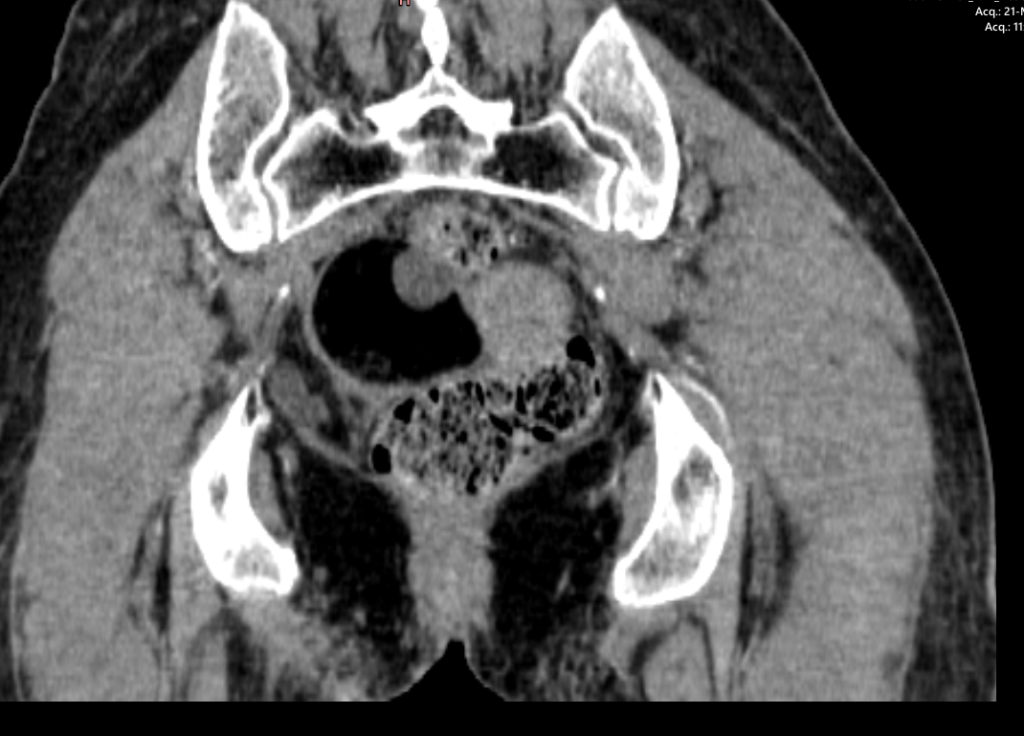

- There is a well defined right adnexal mass which contains mostly fat with two well-defined non enhancing soft tissue nodule along posterior wall and anteromedial wall. The mass measures approximately 5.1 x 4.4 x4.0 cm.

- CECT features are suggestive of right ovarian dermoid cyst

CT findings are suggestive of Right ovarian dermoid cyst.